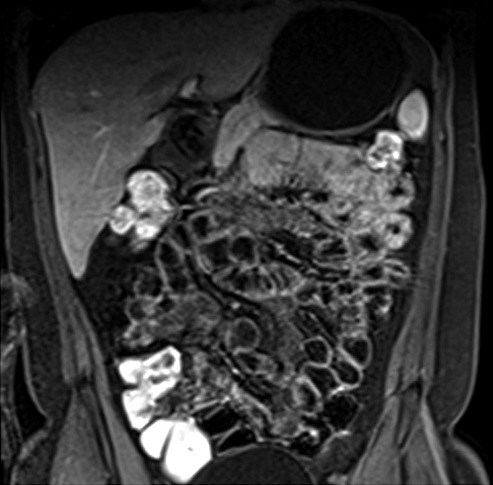

Figura 7

Misma paciente de la figura 6

a y b) Secuencia T2 axial con saturación grasa.

Se observa un grupo de asas en fosa ilíaca derecha de

paredes engrosadas en

forma concéntrica y con edema submucoso (flecha).

c y d) Secuencia de

difusión con valor b 800. E: Mapa de ADC. Se observa

intensa restricción a la

difusión del agua de las asas afectadas. En esta

paciente en quien no se pudo

realizar gadolinio debido a las semanas de gestación se

muestra la importancia

de la difusión en la valoración de actividad

inflamatoria.